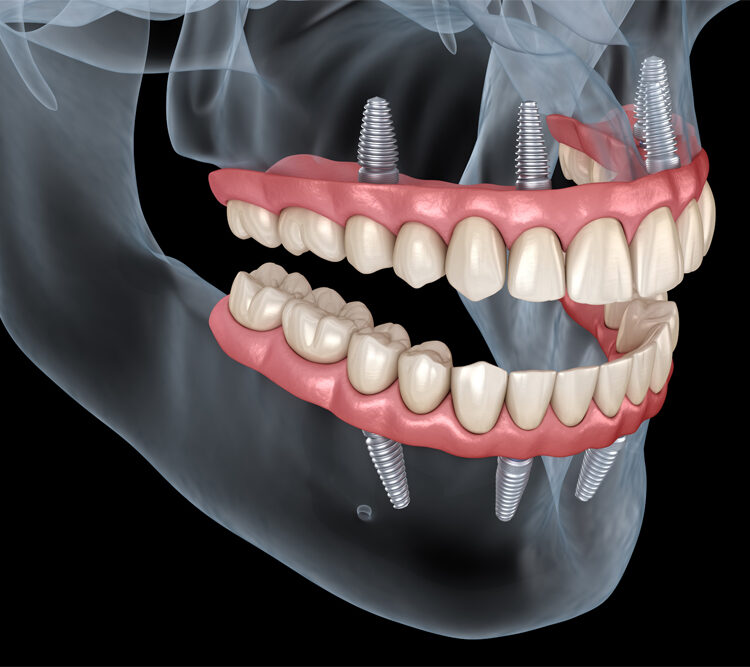

We can restore your smile, as well as speaking & eating ability with advanced prosthetics.A dental implant is a titanium screw that is inserted into the jawbone in place of a lost tooth or teeth, this merges with the bony tissue to serve as a natural tooth root.